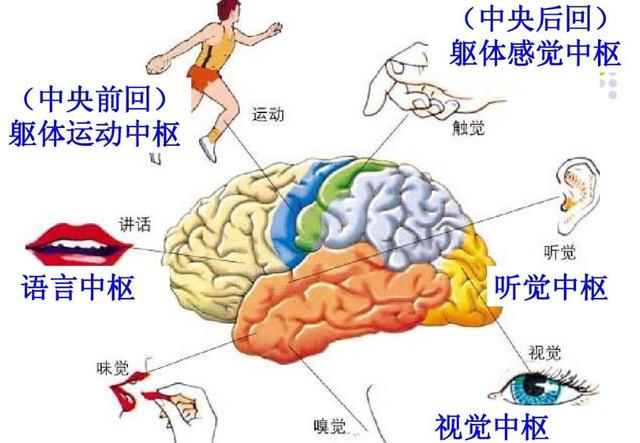

第6 脳血管障害によるもの

特に高齢者では、片腕のしびれや手指のしびれ、手足の脱力を伴う場合には、脳血管障害の発生に注意する必要がある。

4.脳血管疾患

脳血管障害の前駆症状であれ、すでに発症した後の症状であれ、脳血管障害のリスクが高い人にとって、指のしびれは特に注意すべき症状の一つであると言える。ただし、脳血管障害による手指のしびれは、他の症状を伴うことが多く、単独の症状として手指のしびれがみられることもまれではないことを指摘しておく。

まず、脳血管疾患は、指のしびれが原因の脳血管疾患に対して、虚血性脳血管疾患であれば、患者に血行を改善させるだけでなく、栄養神経治療を行うことができ、一般的に患者にイチョウ葉製剤やメチルコバラミン製剤を与えることができます。脳血管障害の急性期であれば、鍼灸治療や漢方薬のイオン導入療法を行うこともできます。

結局のところ、脳に何か問題があるように感じる指を管理することがすべてなのだ。

脳には感覚中枢があり、それは脳の中心にある後回という場所だ。もし問題があれば、それは確実なことを意味する。

主な問題は、小さな脳梗塞、腫瘍の圧迫、頭蓋内血管奇形の圧迫などである。

6.脳梗塞

この病気は、現在、中高年に比較的多い病気で、上肢や手指のしびれが出現することもあり、その原因は、頸動脈圧迫、動脈硬化、脳血栓症などが原因で、脳組織が虚血・低酸素状態になるため、脳神経が障害され、上肢を支配する神経に異常が出現し、それにつながる。